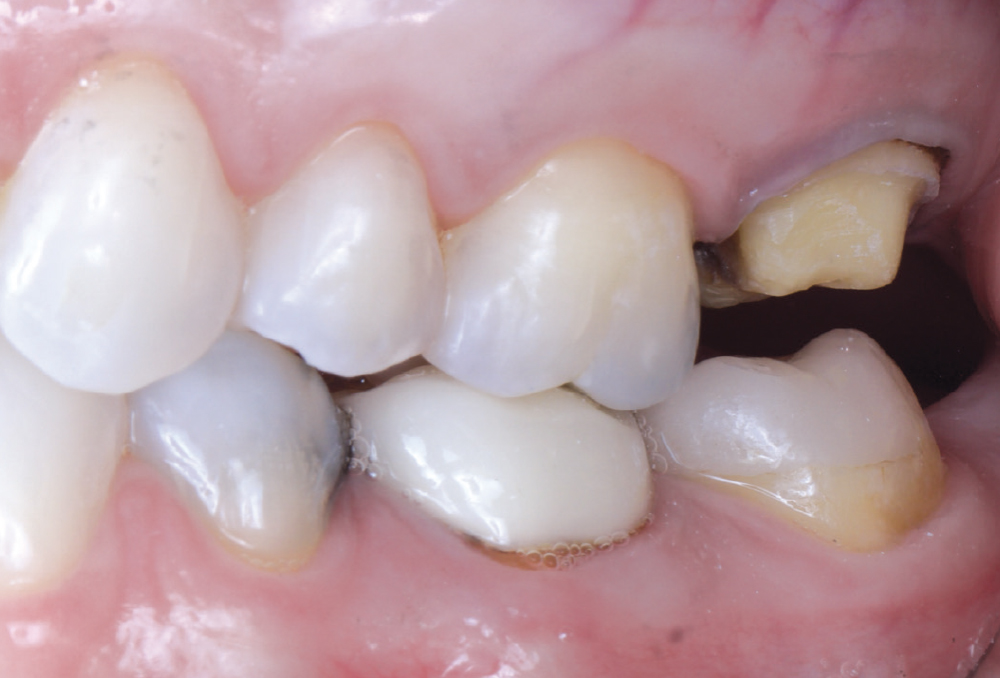

The patient’s chief concern was an open mesial margin of the crown on tooth #15

Figure 1: The patient’s chief concern was an open mesial margin of the crown on tooth #15, which was causing gingival inflammation and shredding her dental floss.

The crown was a 20-year-old Captek™ PFG high-noble bilayered restoration

Figure 2: The crown was a 20-year-old Captek PFG high-noble bilayered restoration.